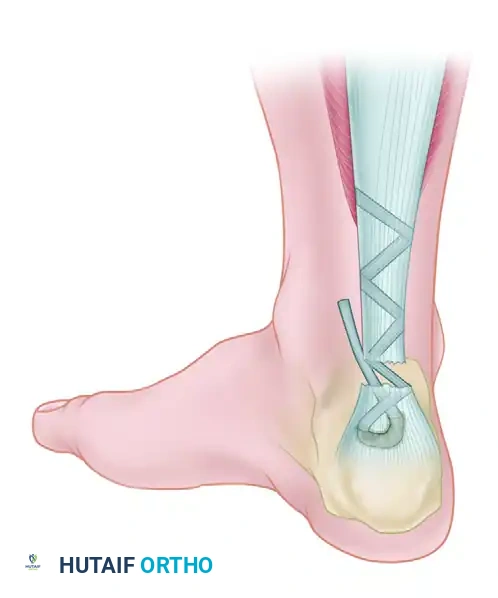

Phase 4: Tendon Weaving and Fixation

- Tendon Passage: Using a suture passer, pull the tag suture of the FHL through the calcaneal tunnel from proximal to distal, exiting the transverse hole.

- Tensioning: Place the ankle in approximately 15 degrees of plantar flexion to set the appropriate resting tension.

- Weaving: Pass the FHL tendon through the tunnel, then route it proximally. Weave the FHL tendon from distal to proximal through the remaining substance of the Achilles tendon (or the aponeurosis) using a tendon weaver. Continue weaving until the full length of the harvested FHL tendon is utilized.

- Securing the Construct: Secure the weave at multiple points using heavy, non-absorbable sutures (e.g., 1-0 Dacron or FiberWire).

- Supplementation (Optional): If the repair requires additional bulk, it can be supplemented using the plantaris tendon or a central turndown slip of the proximal Achilles tendon.